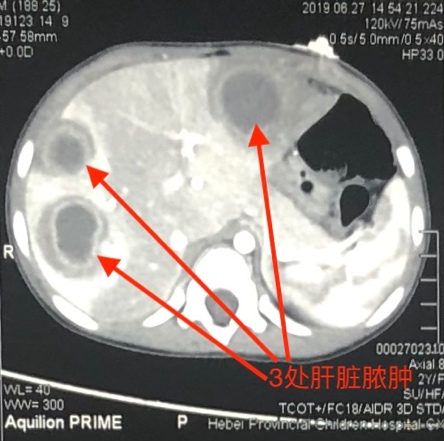

一个3岁小男孩,2周前不明原因出现发热、腹痛,就诊于某儿童医院,给予抗炎治疗数日体温无明显好转,经腹部B超和CT检查诊断肝脏多发脓肿。腹痛持续加重,感染指标居高不下,患儿病情危重,家属为求进一步诊治而来我院,急诊收入小儿外科病房。经讨论,依据B超和CT影像结果分析患儿肝脏已形成三处脓肿,脓腔亦液化成脓,脓壁形成,保守治疗仍不能控制症状,但多发脓肿手术切开引流创伤过大,决定试进行超声引导下穿刺介入治疗,针对肝多发脓肿分别定为穿刺引流脓腔并予以冲洗。手术主要风险在于,穿刺时对正常肝脏造成的损伤和可能导致的大出血,因此,超声监测和穿刺操作是关键。超声科田晖主任医师技术精湛,临床经验丰富,为手术提供了精确定位。

经过多科室协商决定,在患儿入院第二日进行了肝脓肿穿刺引流冲洗手术,麻醉科李晓松主任医师对患儿进行基础麻醉,并严密监测各项生命体征,超声科田晖主任医师予以超声定位,精确描绘出肝脏内三处脓肿的大小、位置、毗邻血管及胆管,并在体表标记穿刺点,详细指明穿刺方向和穿刺深度;小儿外科孙驰主治医师在超声引导下将穿刺针准确刺入肝内脓腔,分别对肝脏多发脓肿进行穿刺引流、脓腔冲洗术,共计抽出脓液约30ml,手术过程顺利,用时20分钟。超声监测显示脓腔内脓液全部被抽出,且肝内大血管及肝内胆管未受损,腹腔内未见明显出血,待患儿麻醉清醒后平安返回病房。术后患儿体温迅速下降至正常,未再发热,患儿腹痛消失,手术当天恢复进食,患儿各项感染指标也逐步恢复正常,复查肝脏超声提示脓肿基本吸收,患儿现已康复出院。